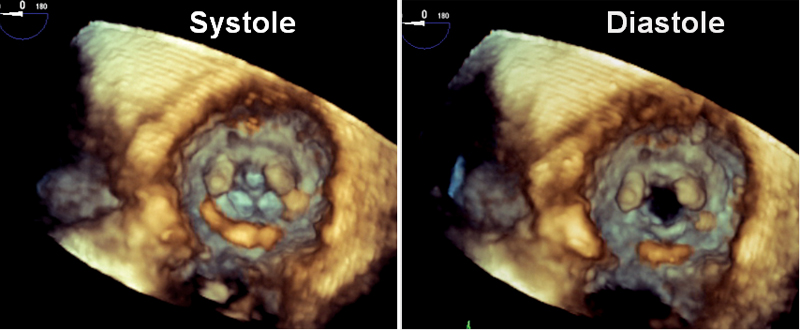

فحوصات تشخيصية لبعض امراض القلب والشرايين التاجية